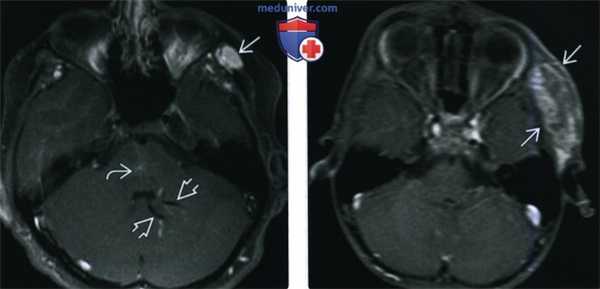

(Слева) Нa поперечной сонограмме верхних отделов шеи визуализируется кистозное объемное образование смешанной структуры с расширенными синусоидами и эхогенным флеболитом, наличие которого позволяет сделать вывод о венозной мальформации. Тем не менее, УЗИ не позволяет оценить распространенность больших мальформаций в глубокие отделы шеи или подтвердить множественность (из статьи на сайте «Лучевая диагностика: УЗИ»).

(Справа) На поперечной сонограмме у ребенка с безболезненным объемным образованием в нижних отделах шеи визуализируется кистозный очаг с ровными краями: расширенное синусоидальное пространство с небольшими включениями дебриса и перегородками внутри. Обратите внимание на заднее акустическое усиление - признак кистозной природы образования.